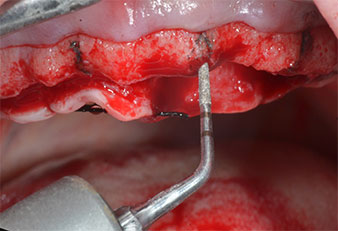

Пиезоелектрически инструмент с диамантено покритие с форма на пламък (Piezomed I1) e използван за маркиране на позициите на имплантите и за пилотна подготовка (Фиг. 3). Препарацията беше извършена с внимателни вертикални движения, с намалена мощност, пълна иригация и лек натиск (под 300 g) След това се приложи пилотен инструмент (Piezomed I2A/ I2P) за първоначално увеличение на диаметъра на имплантното ложе с 2 mm (Фиг. 4), последвано от 3 mm разширение (Фиг. 5)

В случай на твърда кост, цялата поредица от инструменти, включително междинните инструменти Piezomed Z25P и Z35P, трябва да се използват за разширяване на остеотомиите.

Те също така са предназначени за подготовка в близост до синусовата мембрана във връзка с вътрешни аугметационни процедури или когато има по-малко от 4 mm остатъчна височина на костта.

В настоящия случай инструменти Z25P и Z35P не са използвани поради сравнително меката задна кост, която лесно се обработва с I3A/I3P.